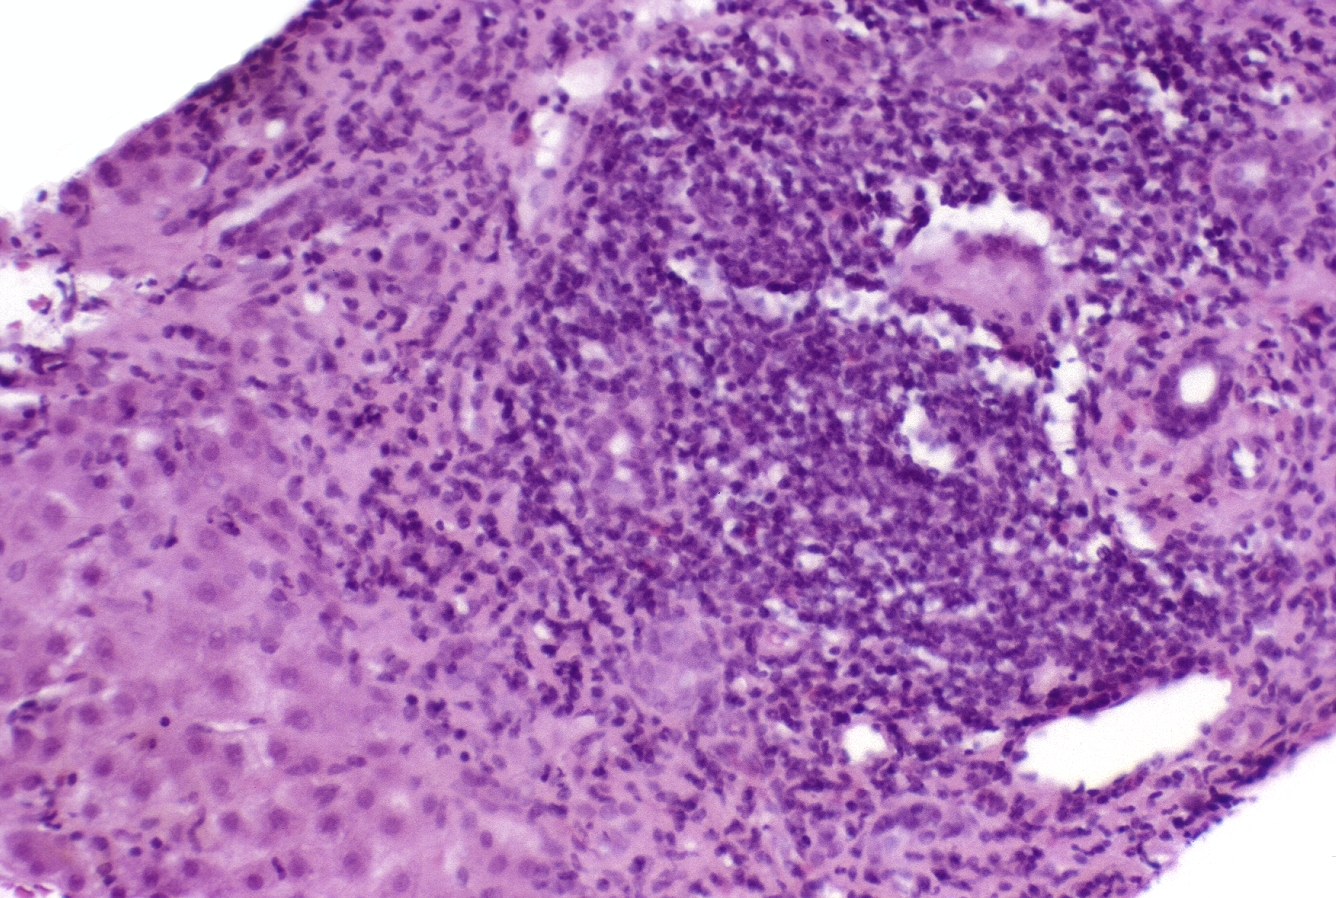

HISTOLOGY: HEPATOBILIARY: LIVER: BILIARY: autoimmune hepatitis